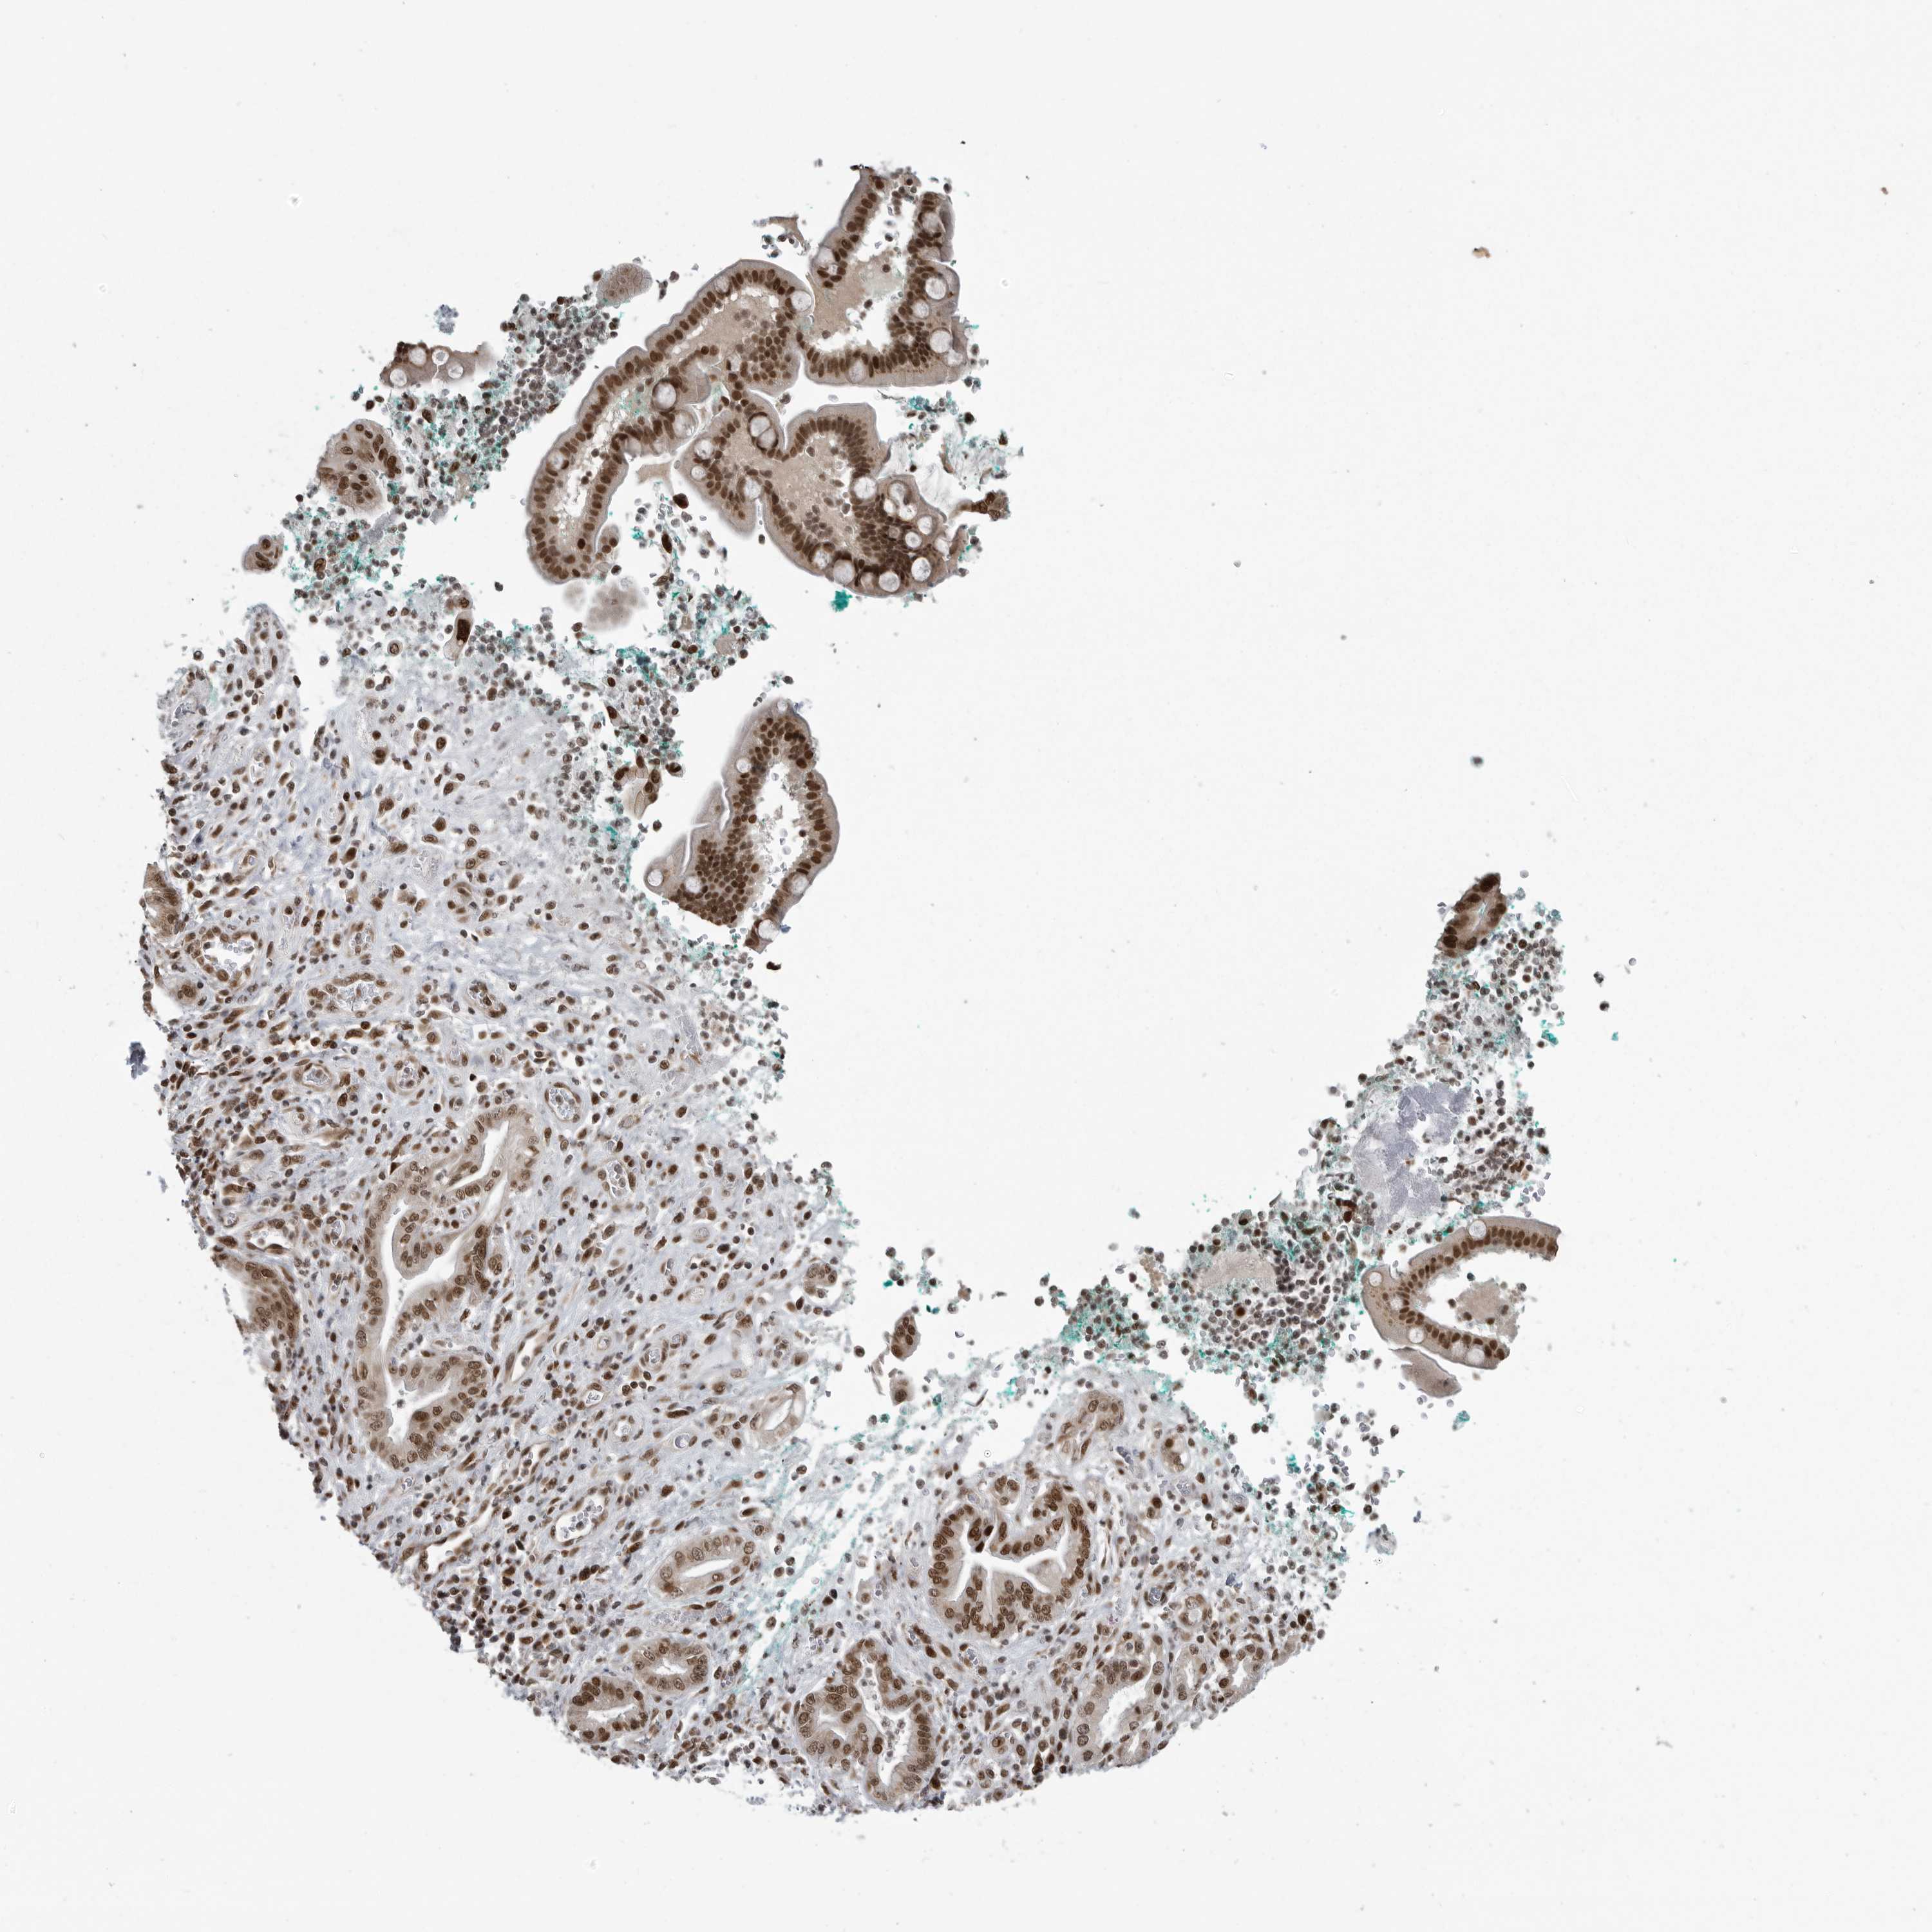

PANCREATIC CANCER - Protein expressioni

A mouse-over function shows sample information and annotation data. Click on an image to view it in a full screen mode. Samples can be filtered based on level of antibody staining by selecting one or several of the following categories: high, medium, low and not detected. The assay and annotation is described here.

Note that samples used for immunohistochemistry by the Human Protein Atlas do not correspond to samples in the TCGA dataset.

Antibody stainingi

Antibody staining in the annotated cell types in the current human tissue is reported as not detected, low, medium, or high, based on conventional immunohistochemistry profiling in selected tissues. This score is based on the combination of the staining intensity and fraction of stained cells.

Each image is clickable and will lead to virtual microscopy that enables deeper exploration of all samples and also displays staining intensity scores, fraction scores and subcellular localization as well as patient and tissue information for each sample.

Antibody HPA026867

Staining

High

Medium

Low

Not detected

Intensity

Strong

Moderate

Weak

Negative

Quantity

>75%

75%-25%

<25%

None

Location

Nuclear

Cytoplasmic/membranous

Cytoplasmic/membranous,nuclear

Adenocarcinoma, NOS